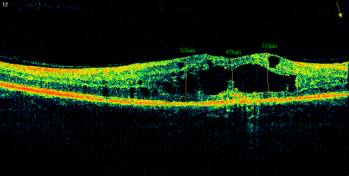

Illustration 2. OCT of the macula and fundus of the right eye of the patient P. 52

years old, diagnosed with PPDR, diffuse cystic macular edema.